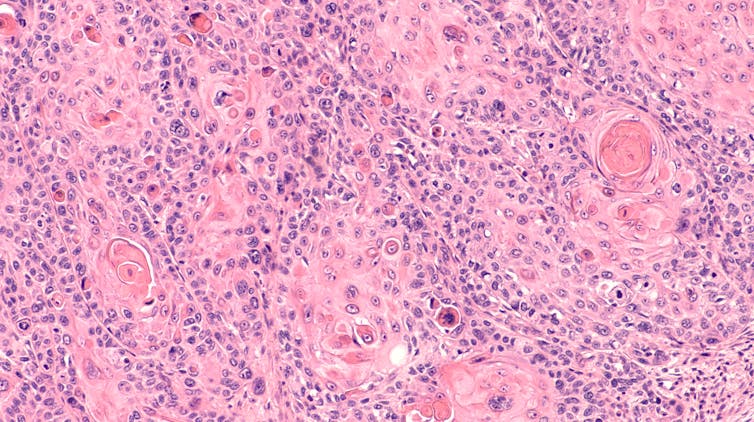

De las implicaciones del VPH con los diferentes cánceres, la mejor definida es la del cáncer de cuello uterino. El cancer de cuello de útero es el cuarto tipo de cáncer más frecuente entre las mujeres.

Sin embargo, entre un 10 y un 15 % de los casos el VPH no se eliminará y persistirá durante décadas. La persistencia viral es la condición necesaria para que aparezcan lesiones premalignas. Si estas lesiones no se diagnostican precozmente y no se tratan, puede aparecer un cáncer.

El tratamiento de estas lesiones (habitualmente mediante la extirpación de una parte del cuello de útero o conización) permite prevenir su progresión y el desarrollo del cáncer. Hasta la actualidad, el cribado del cáncer de cuello de útero se ha basado en la citología.